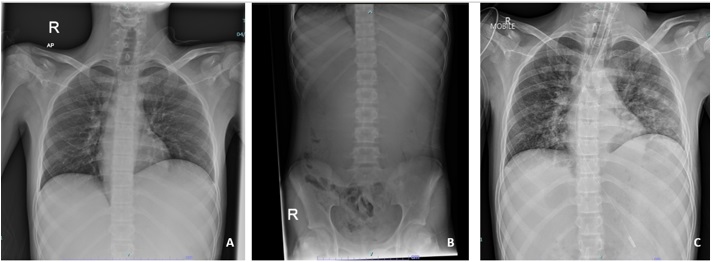

FIGURE 1: (A) Chest radiograph revealed an elevated left hemidiaphragm with absent of gastric bubble; (B) Abdominal radiograph revealed a paucity of small bowel gases that suggest proximal intestinal obstruction; (C) Chest radiograph taken post-intubation revealed bilateral alveolar opacities after the patient aspirated